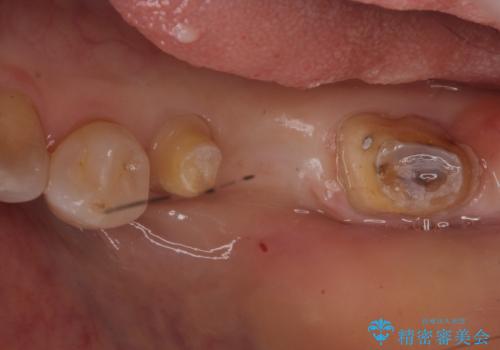

- 左下奥歯の歯ぐきの違和感で来院。

昔神経の治療をした歯が割れてしまっていました。

やむなく抜歯になりましたが、その部分にインプラントを始め希望されましたが、炎症により、骨がなく、かつ歯並びの関係で入れても歯ブラシができずにインプラントも長くもたなそうという診断になりました。